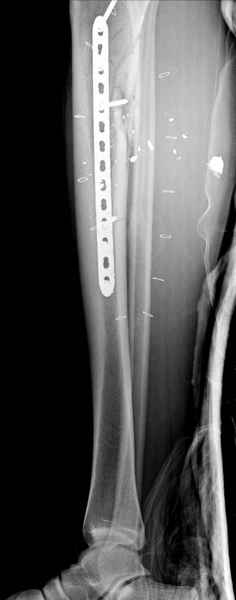

1 неполный перелом большеберцовой кости перкутанная пластина